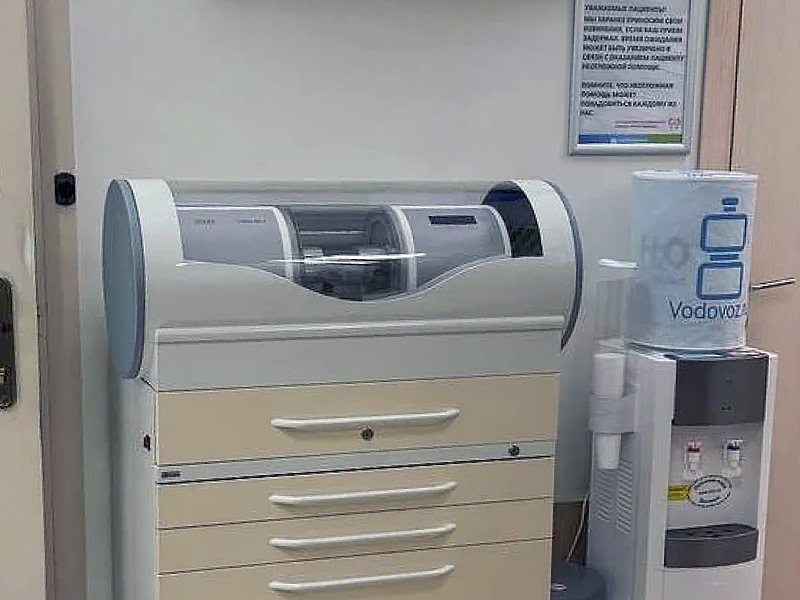

Центр экспертной ортодонтии и цифровой стоматологии

- Инвизалигн (Invisalign) – съемные прозрачные капы из пластика, невидимая на зубах, удобные в ношении, поэтапно изменяющие прикус в лучшую сторону. На время принятия пищи их снимают.

- ClearCorrect – американский бренд, высококачественные капы для выравнивания зубов созданы по самым современным технологиям и постепенно выравнивают самые сложные изменения прикуса.

- SmartTrack – съемные ортодонтические устройства из гипоаллергенного биопластика, упругие и эластичные, плотно прилегающие к зубам.

- SureSmile Aligners – прозрачные конструкции производят на основе суперточных сканирований, с невероятной точностью.

- Clarity Aligners – продукция американской компании 3M Unitek, производителя ортодонтической продукции на протяжении более 80 лет.

- OrthoCaps немецкий бренд стоматологической продукции, широко известный во всем мире.